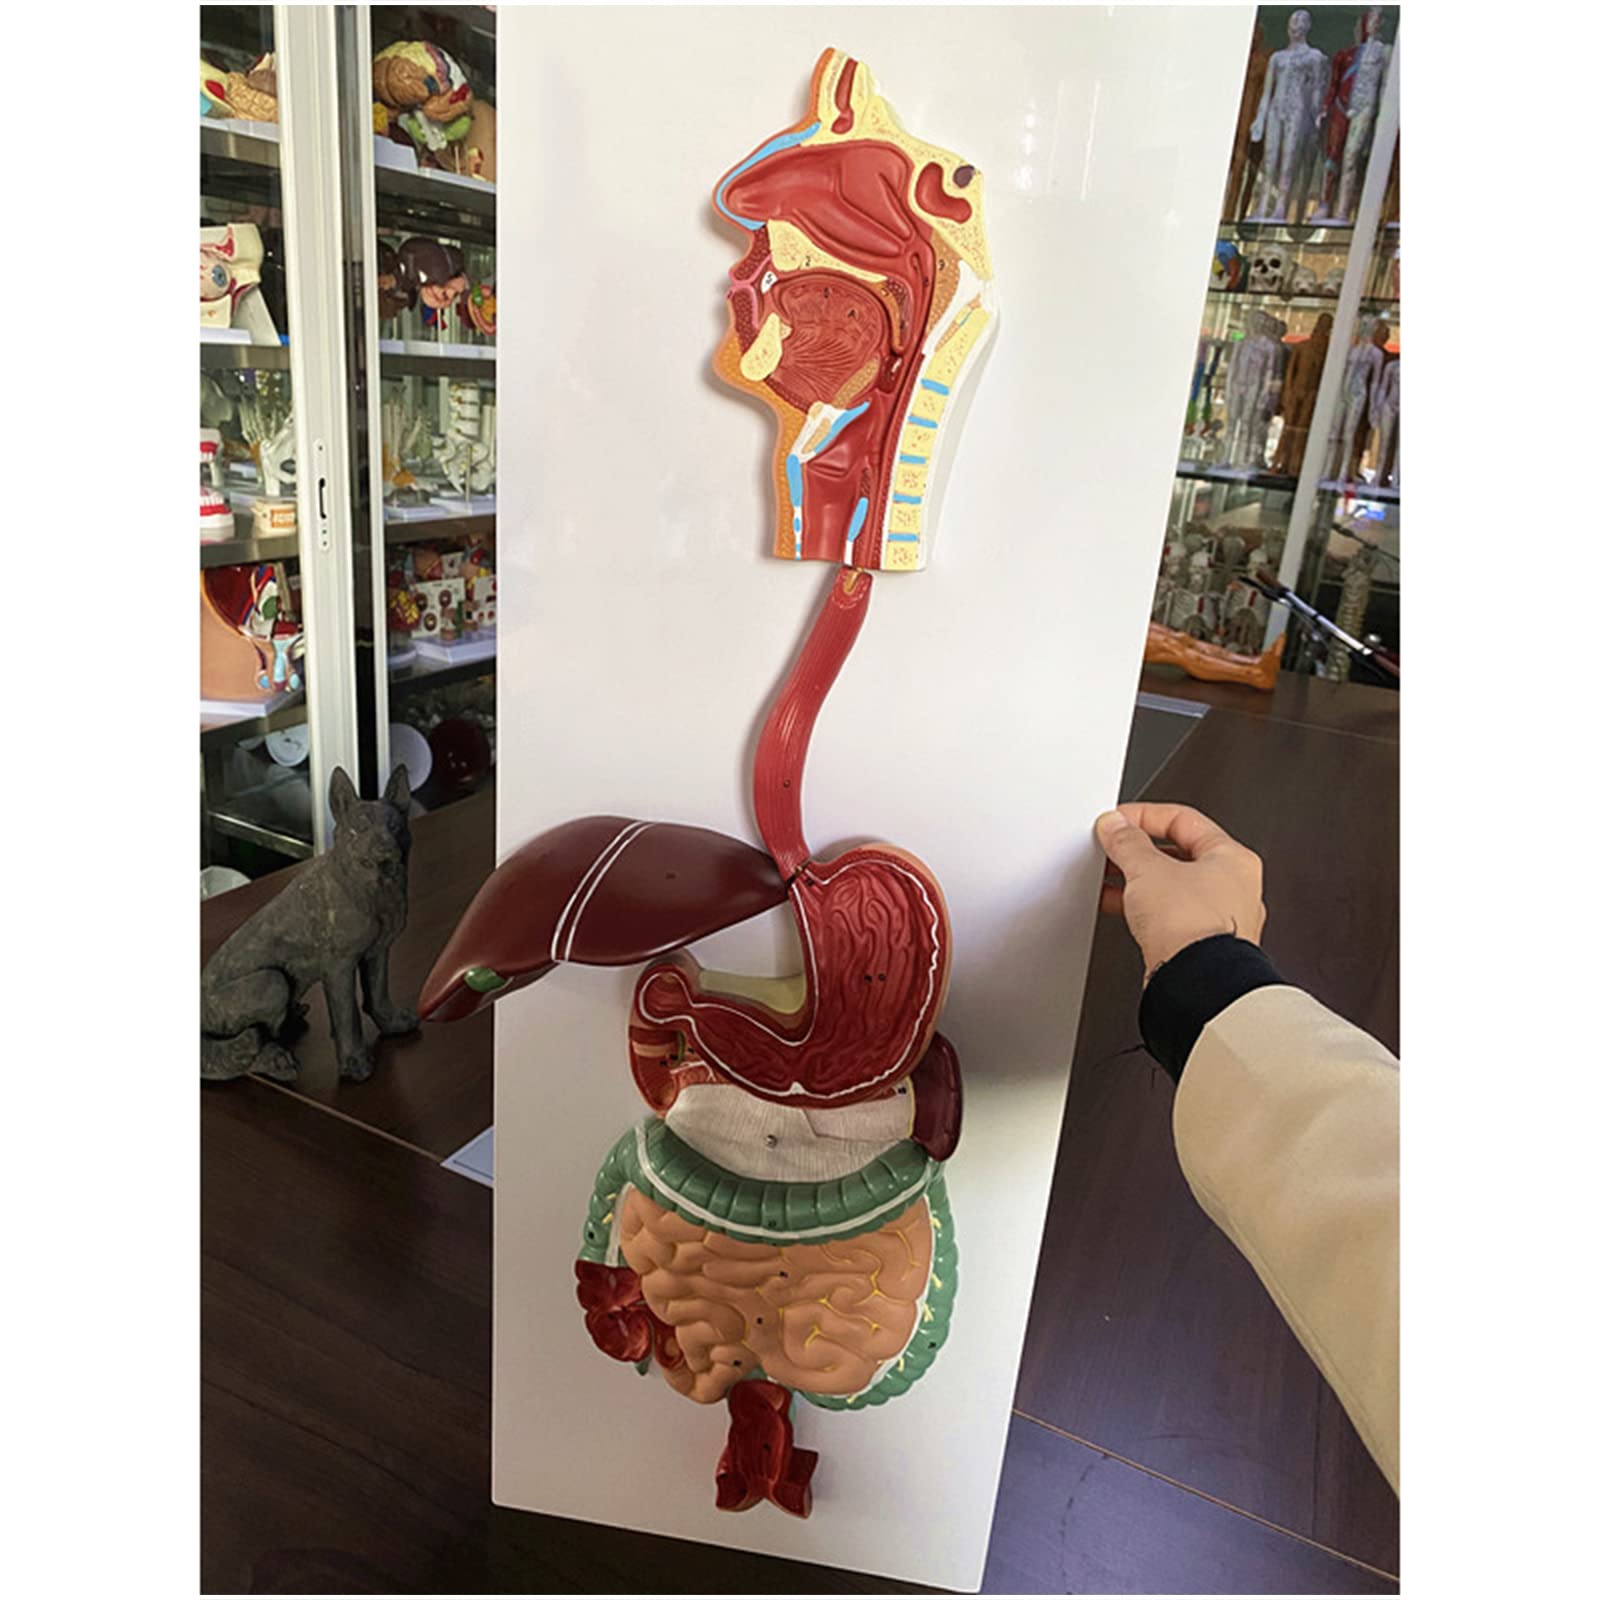

- INTERACTIVE LEARNING EXPERIENCE - Disassemble and explore the digestive system like never before!

The Human Digestive System Model is a life-size, three-dimensional representation of the human digestive tract, designed for educational purposes. It features disassemblable parts for interactive learning and is made from durable, anti-corrosive PVC material, making it an essential tool for anatomy students, educators, and healthcare professionals.